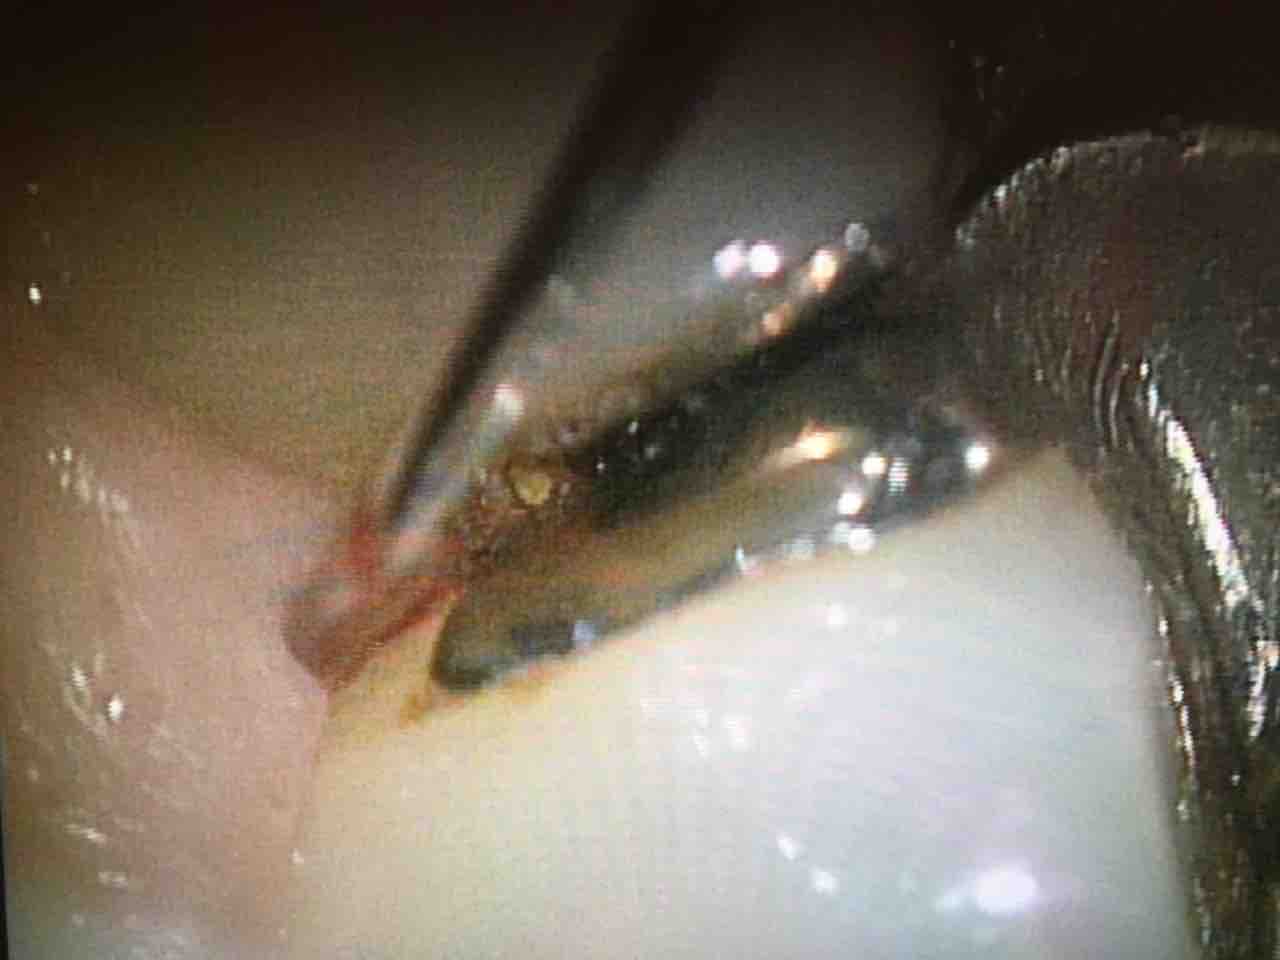

見えるって凄い!!大変だけど結構好きです。見えない世界の歯石をとるの♡

見えといっても、歯周ポケットの幅は健康で締まっていれば1mmあるかないかです。

今日のケースでも、0.8mm程度

1mm無い歯と歯肉の間。そして見える角度は限られて、更に器具の角度、挿入方向も限られる...

歯科用顕微鏡の処置は非常に制限される処置なのです

拡大した視野でも、その処置を行うのは私の実際の手です。私の手が0コンマ...の処置を行うのです。

シビアとしか言いようがありません